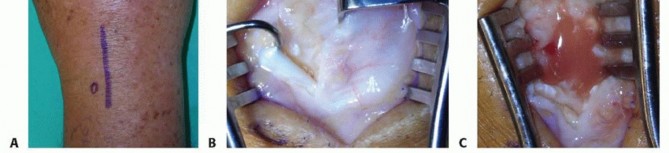

The MCP joint is most reliably approached via a dorsal longitudinal incision. This approach provides excellent visualization of the joint capsule and allows for extensive irrigation while avoiding the palmar neurovascular bundles.

1. Incision and Dissection: A 3-cm dorsal longitudinal incision is made centered over the affected MCP joint. Subcutaneous tissues are bluntly dissected to protect the dorsal sensory venous network.

2. Extensor Mechanism Management: The extensor tendon is identified. To access the joint, the sagittal band is incised longitudinally on either the radial or ulnar side of the extensor tendon. The tendon is then gently retracted to the contralateral side using a Ragnell or Senn retractor.

3. Capsulotomy and Debridement: A longitudinal capsulotomy is performed. Immediately upon breaching the capsule, purulent fluid will typically egress. Swab cultures should be taken at this precise moment if preoperative aspiration was unsuccessful.

4. Irrigation: The joint is aggressively irrigated with a minimum of 1 to 2 liters of sterile normal saline. A small rongeur or curette is used to meticulously debride any fibrinous exudate, necrotic synovium, and debris from the articular gutters.

Image